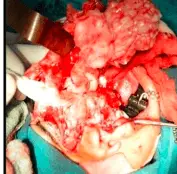

PATIENT UNDERWENT HEMI-MAXILLECTOMY-LEFT SIDE USING WEBER FERGUSSON INCISION UNDER G.A. SUPERIORLY, THE FLOOR OF THE LEFT ORBIT WAS NOT INVOLVED IN THE LESION. INFERIORLY, THE LESION INVOLVED THE LEFT ALVEOLAR RIDGE AND TEETH. MEDIALLY, THE LEFT NASAL FLOOR WAS INVOLVED AND THE NASAL SEPTUM WAS INTACT. LATERALLY, THE BUCCAL CORTICAL BONE WAS INVOLVED. ANTERIORLY, THE ANTERIOR WALL OF MAXILLA WAS INVOLVED IN THE LESION AND POSTERIORLY, THE POSTERIOR WALL OF MAXILLA WAS INTACT. PRIMARY CLOSURE WAS ACHIEVED USING 4-0 VICRYL SUTURE FOR MUCOSA. SKIN CLOSURE WAS DONE USING 4-0 PROLENE SUTURE AND DERMABOND. THE SURGICAL SPECIMEN WAS SENT FOR BIOPSY WHICH REVEALED AMELOBLASTIC FIBROMA.

INTRA-OPERATIVE PICTURES